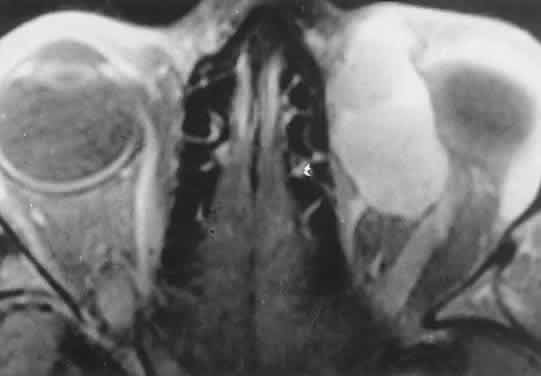

Acute blood cyst formation in this age group makes the distinction between a pre-existent but clinically silent lymphangioma and a rapidly emerging rhabdomyosarcoma a common orbital diagnostic problem. Evidence suggesting an orbitallymphangioma includes the variable finding of conjunctival or eyelid components of the malformation.86 Conjunctival lesions appear as ectatic channels filled with clear or hemorrhagic fluid. Eyelid ecchymosis may result from the seepage of blood out of the thin-walled orbital cysts. Additional developmental anomalies of the eye and adnexa may be present. Other head and neck involvement may be manifest as local hypertrophy (e.g., of the cheek or lips), and cystic palatal lesions may be seen. CT discloses a single or multilobulated mass, which represents only the blood cyst portion of the tumor (Fig. 14). Individual lobules may have different radiodensities depending on the presence of clots or liquefied blood within each cyst (Fig. 15). A generalized increase in orbital dimensions suggests a long-standing, probably congenital process. Echography may help differentiate the cystic components of lymphangioma from cellular rhabdomyosarcoma. Echography shows the blood cysts to be acoustically inactive spaces, with extremely low internal reflectivity (Fig. 16). Clots within the cysts can increase internal heterogeneity, however. MRI has virtually eliminated the need for diagnostic biopsy in this condition, because of its ability to show differing magnetic properties of suspended, degrading blood products (Fig. 17).